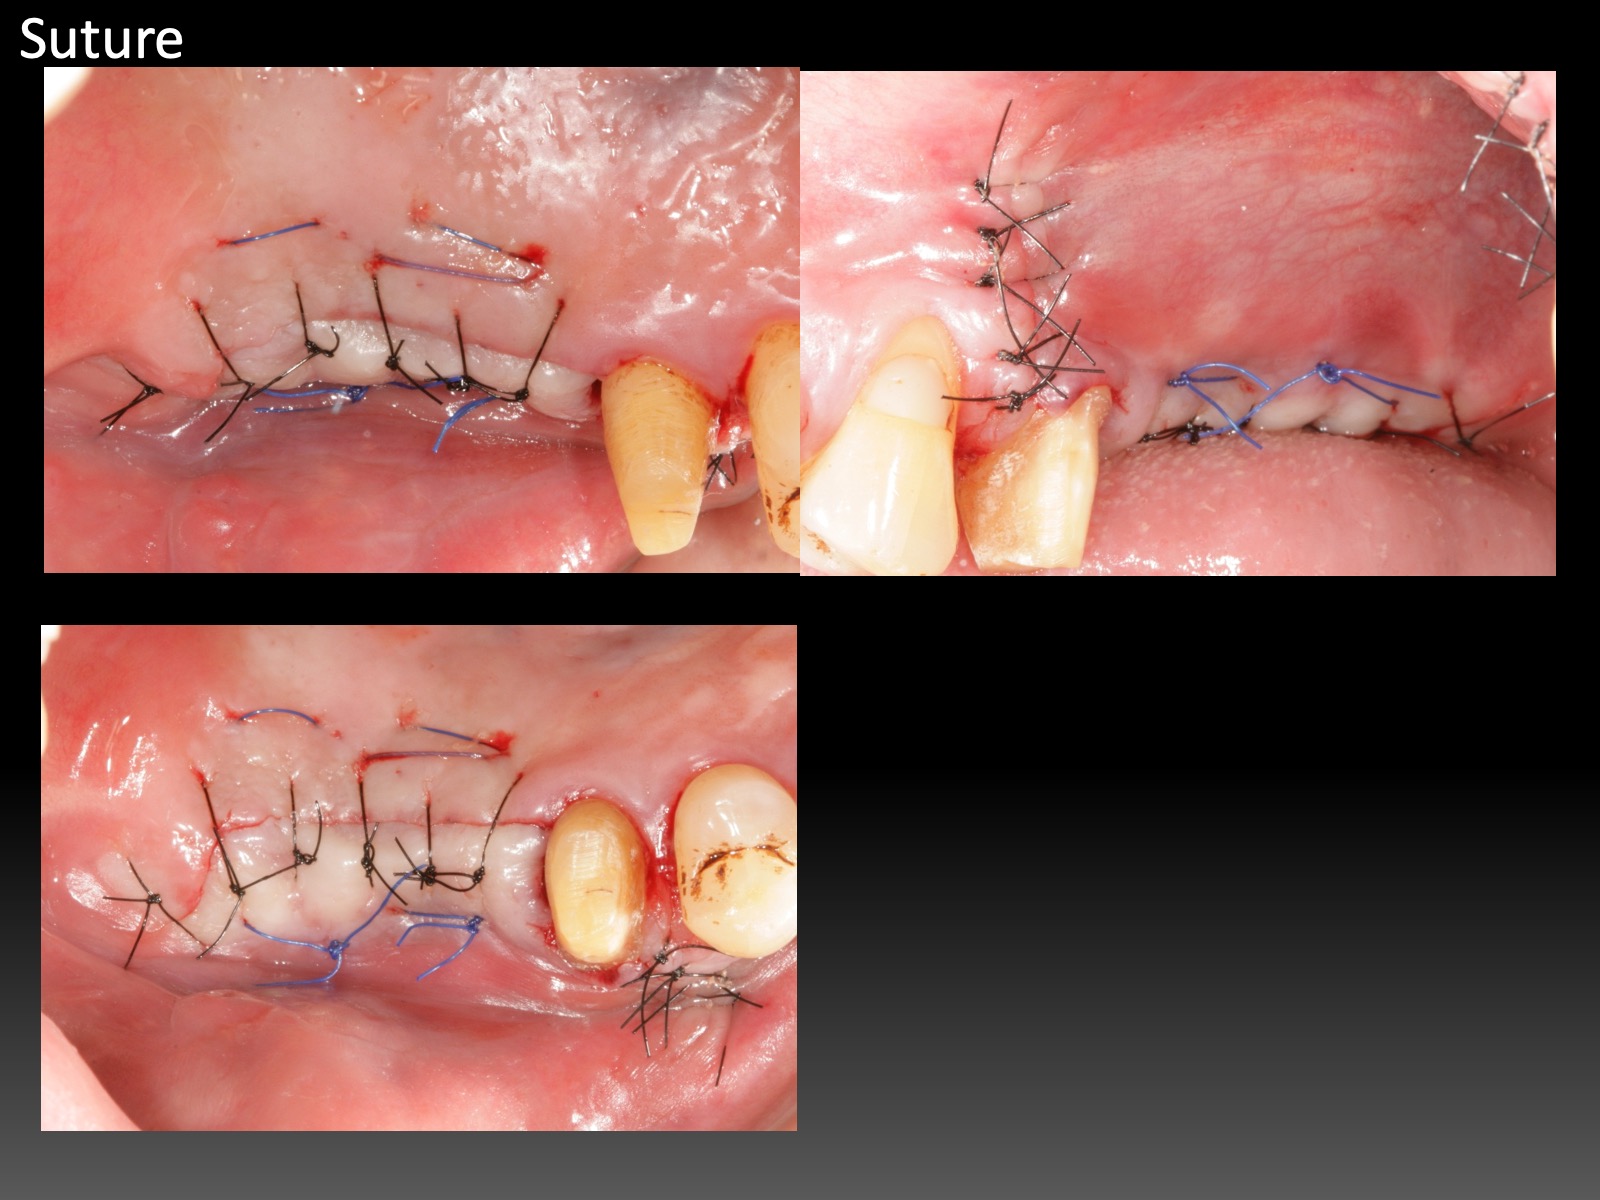

Increase Keratinized Tissue of Lingual Aspect 增加舌側角化組織

GBR的舌側提升,會讓內側角化組織變少,或是,案例即使沒補骨,原本就舌側角化組織缺乏。這幾年自己也想解決這個難題。試了幾個不同做法,有一些心得。

一開始的Partial Thickness皮瓣移動,只須刀片劃開表層,其餘用鈍器械推下去。跟Tension free flap release這篇的手法類似。意即,切得少,推得多。

固定的關鍵,這幾年我發現,是縫針。因為有舌頭會移動,空間小,不易操作,而且進針、取針時機很短。縫針找1/2彎度,短如10mm,短進短出,要快,沒有多餘時間再找針頭。針還要利,故角針遠比圓針更好。個人經驗,縫針規格,3/8 彎度,13mm以上,也可以,但是會增加手術難度。短、勾、銳,很重要。

還有另一個固定的技巧。一開始graft容易滑動,用針進出graft,不容易固定。不如專注在cross mattress進出旁邊的骨膜上,利用縫線先將graft壓住。縫到尾聲再用針進出graft,做最後固定。